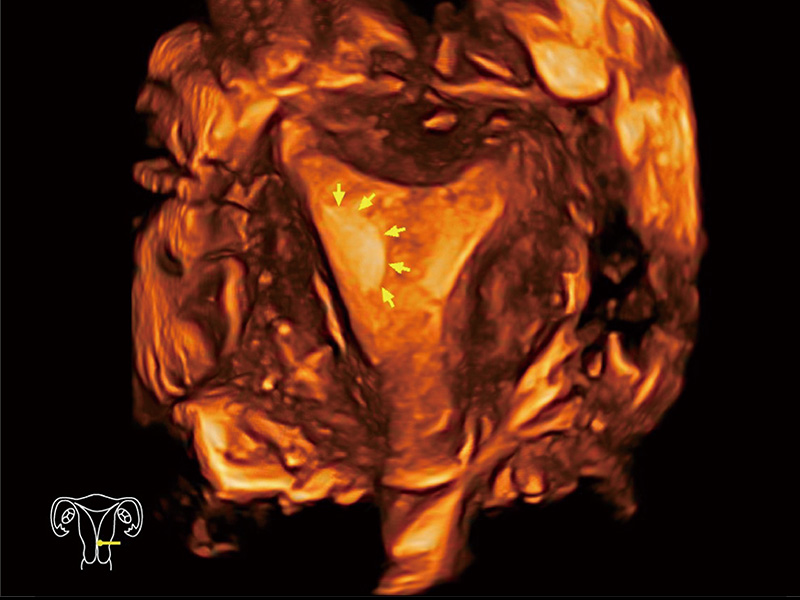

中央型宫腔粘连